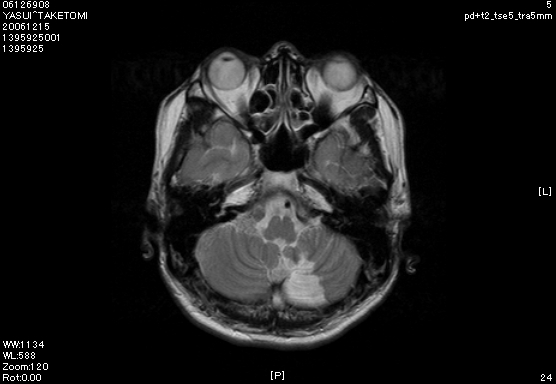

そんな、平成18年11月下旬の月曜日の朝。前日もセミナーに参加し、今週も頑張っていこうと家を出ようとした矢先、突然とてつもないめまいに襲われました。何とか外を数歩歩くものの、壁伝いでなければとても前に進めない状態です。診療ができる状態ではなかったので、そのまま家に引き返し、急いで脳神経外科へ行きました。すぐにMRIを撮ってもらい、小脳梗塞と診断され、そのまま入院となりました。あと2週間ほどで37歳になるというときでした。生まれてはじめての入院(生まれた時は未熟児だったので、その時がはじめての入院かもしれませんが笑)。家族には心配をかけたし、オリエント歯科スタッフも困らせてしまいました。そして、通院していた患者さんたちにもご迷惑をおかけしてしまいました。結局ひと月ほど入院しましたが、幸い後遺症などもなく、日常生活や診療も問題ない状態で退院することができました。今まで当たり前のように感じていた、健康でいることのかけがえのなさを身に染みて感じました。また、入院していた病院の看護師さんらの献身的な対応に非常に感銘を受けました。